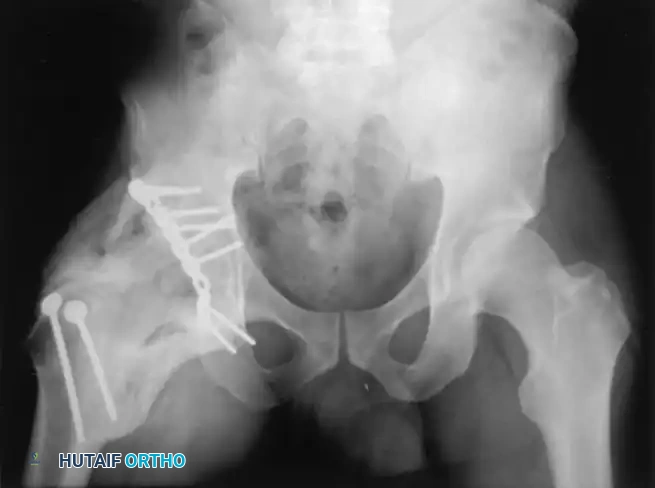

Heterotopic Ossification (HO)

Heterotopic ossification—the formation of mature lamellar bone in non-osseous soft tissues—is a frequent complication following surgical trauma to the hip abductors.

- Incidence by Approach: HO occurs most frequently after extensile approaches (e.g., extended iliofemoral), with moderate-to-severe HO (Brooker grades III and IV) occurring in 14% to 50% of patients without prophylaxis. Following the Kocher-Langenbeck approach, the rate is approximately 25%. It is exceedingly rare after the ilioinguinal approach unless the external surface of the ilium is aggressively stripped.

FIGURE 56-35: Brooker grade IV heterotopic ossification occurred despite postoperative irradiation, demonstrating complete bony ankylosis of the hip joint.